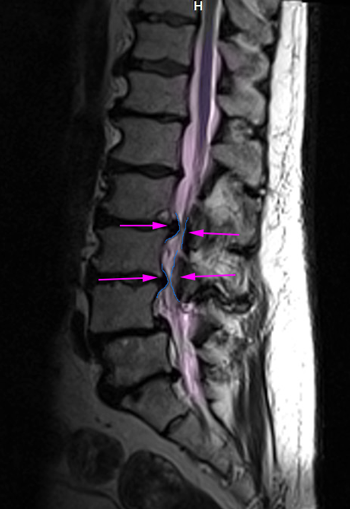

Αριστερά: Στένωση οσφυϊκού σπονδυλικού σωλήνα. Δεξιά:Φυσιολογικό νευρικό τρήμα στην κορυφή (πράσινο) με ελεύθερο νεύρο στο κέντρο (μπλέ περίγραμμα). Στενό τρήμα (κυανό βέλος) και ουσιαστικά κλειστό τρήμα,το οποίο εμπεριέχει μόνο το πιεσμένο νεύρο (πράσινο βέλος). Τεμάχιο δισκοκήλης εντός του τρήματος (κόκκινο περίγραμμα).